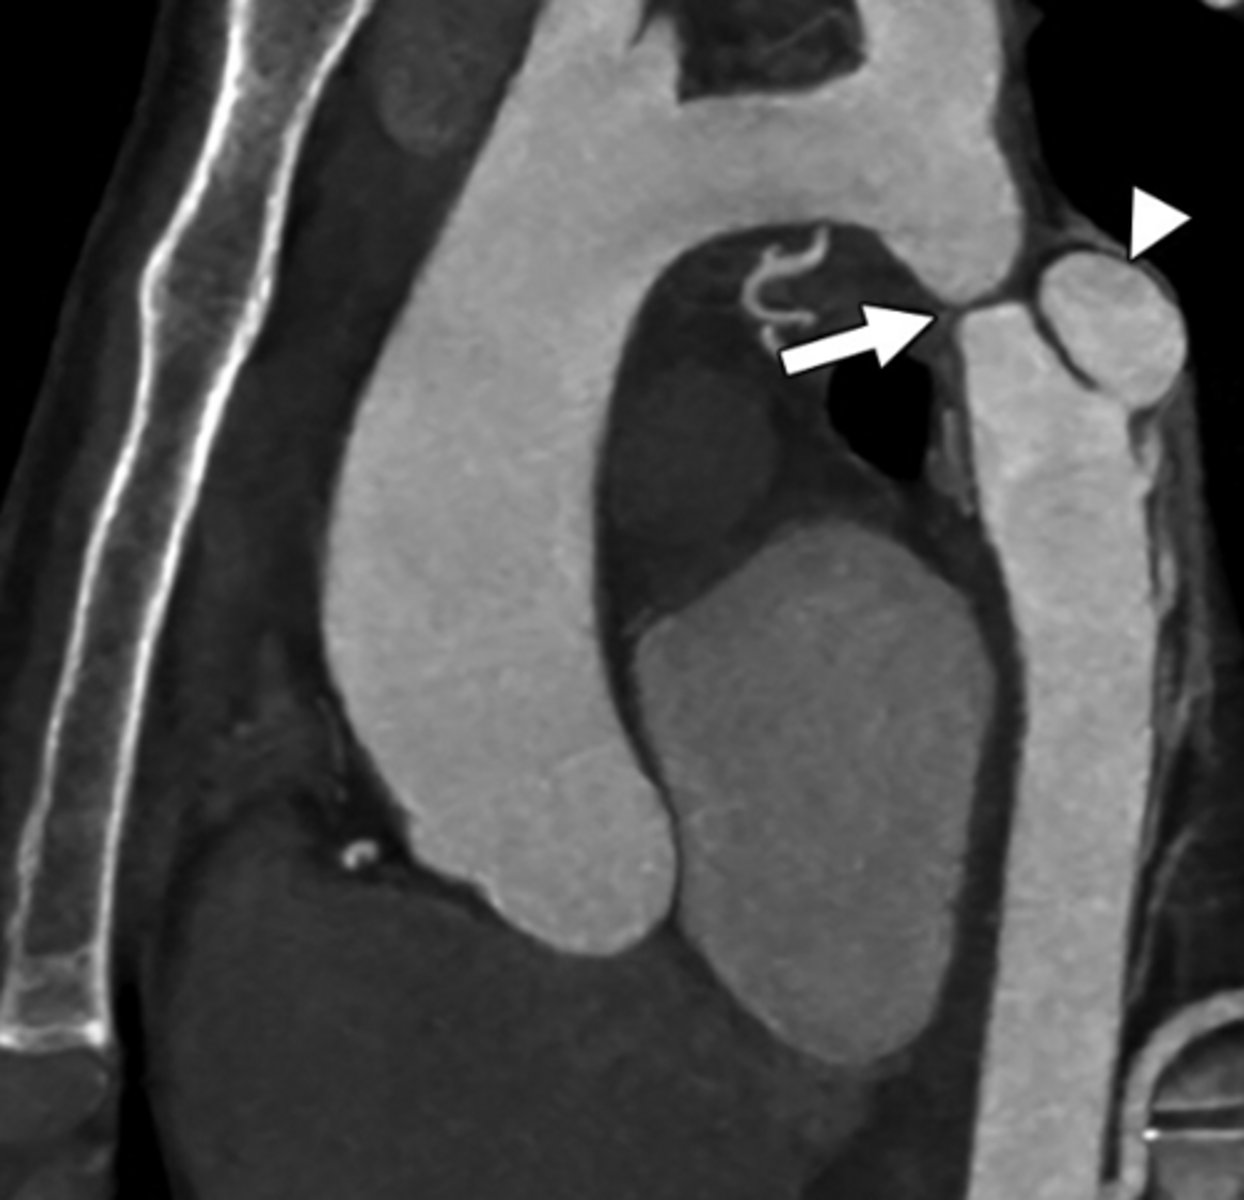

What is patent ductus arteriosus (PDA)?

Persistent connection between the pulmonary artery and aorta after birth.

<p>Persistent connection between the pulmonary artery and aorta after birth.</p>

What is coarctation of the aorta?

Congenital narrowing of the aorta.

<p>Congenital narrowing of the aorta.</p>

What are the key features of infantile coarctation of the aorta?

Symptomatic in early childhood, tubular hypoplasia of the aortic arch, occurs proximal to a PDA.

<p>Symptomatic in early childhood, tubular hypoplasia of the aortic arch, occurs proximal to a PDA.</p>

What are the key features of adult coarctation of the aorta?

Narrowing opposite a closed ductus arteriosus, distal to the great vessels from the aortic arch.

<p>Narrowing opposite a closed ductus arteriosus, distal to the great vessels from the aortic arch.</p>

What is the chest radiograph finding in coarctation of the aorta?

Figure 3 sign.

<p>Figure 3 sign.</p>